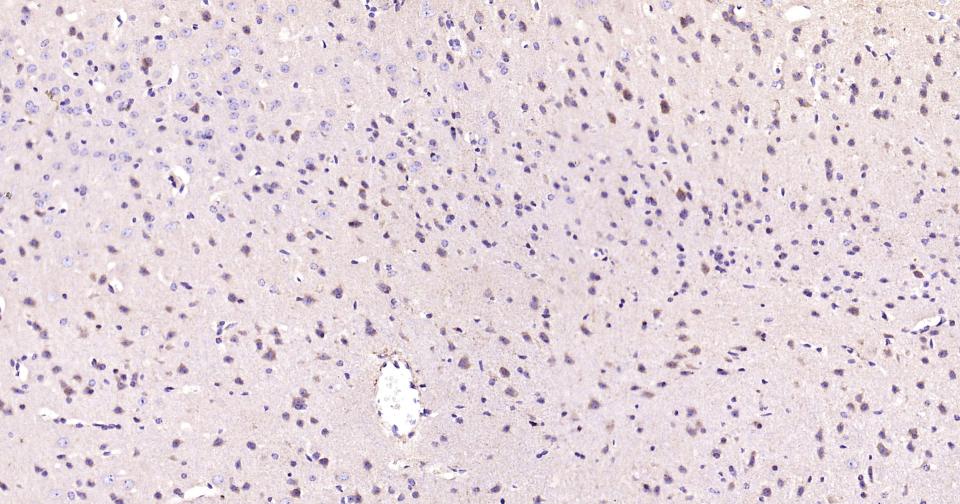

Paraformaldehyde-fixed, paraffin embedded Human Cerebrum; Antigen retrieval by boiling in sodium citrate buffer (pH6.0) for 15 min; Antibody incubation with PIK3C3 Monoclonal Antibody, Unconjugated(bsm-61161R) at 1:200 overnight at 4°C, followed by conjugation to the SP Kit (Rabbit, SP-0023) and DAB (C-0010) staining.